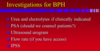

What investigations should you do if you suspect a patient has BPH?

- Urinary frequency and volume chart for all with LUTS

- Urinalysis to rule out infection

- Post-void bladder scan for chronic retention

- PSA

- US to assess prostate and look for any hydronephrosis/retention. Enlarged if prostate>30ml

- Urodynamic studies with BOOI to look for obstruction